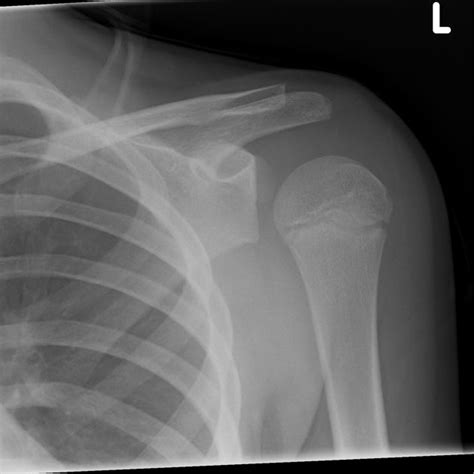

Lightbulb Sign - Shoulder Dislocation | | Shoulder Dislocation

shoulder dislocation posterior sign radiology head radiopaedia pediatric humeral ap lightbulb humerus radiograph normal dislocated abnormal lateral appearance signs overlap